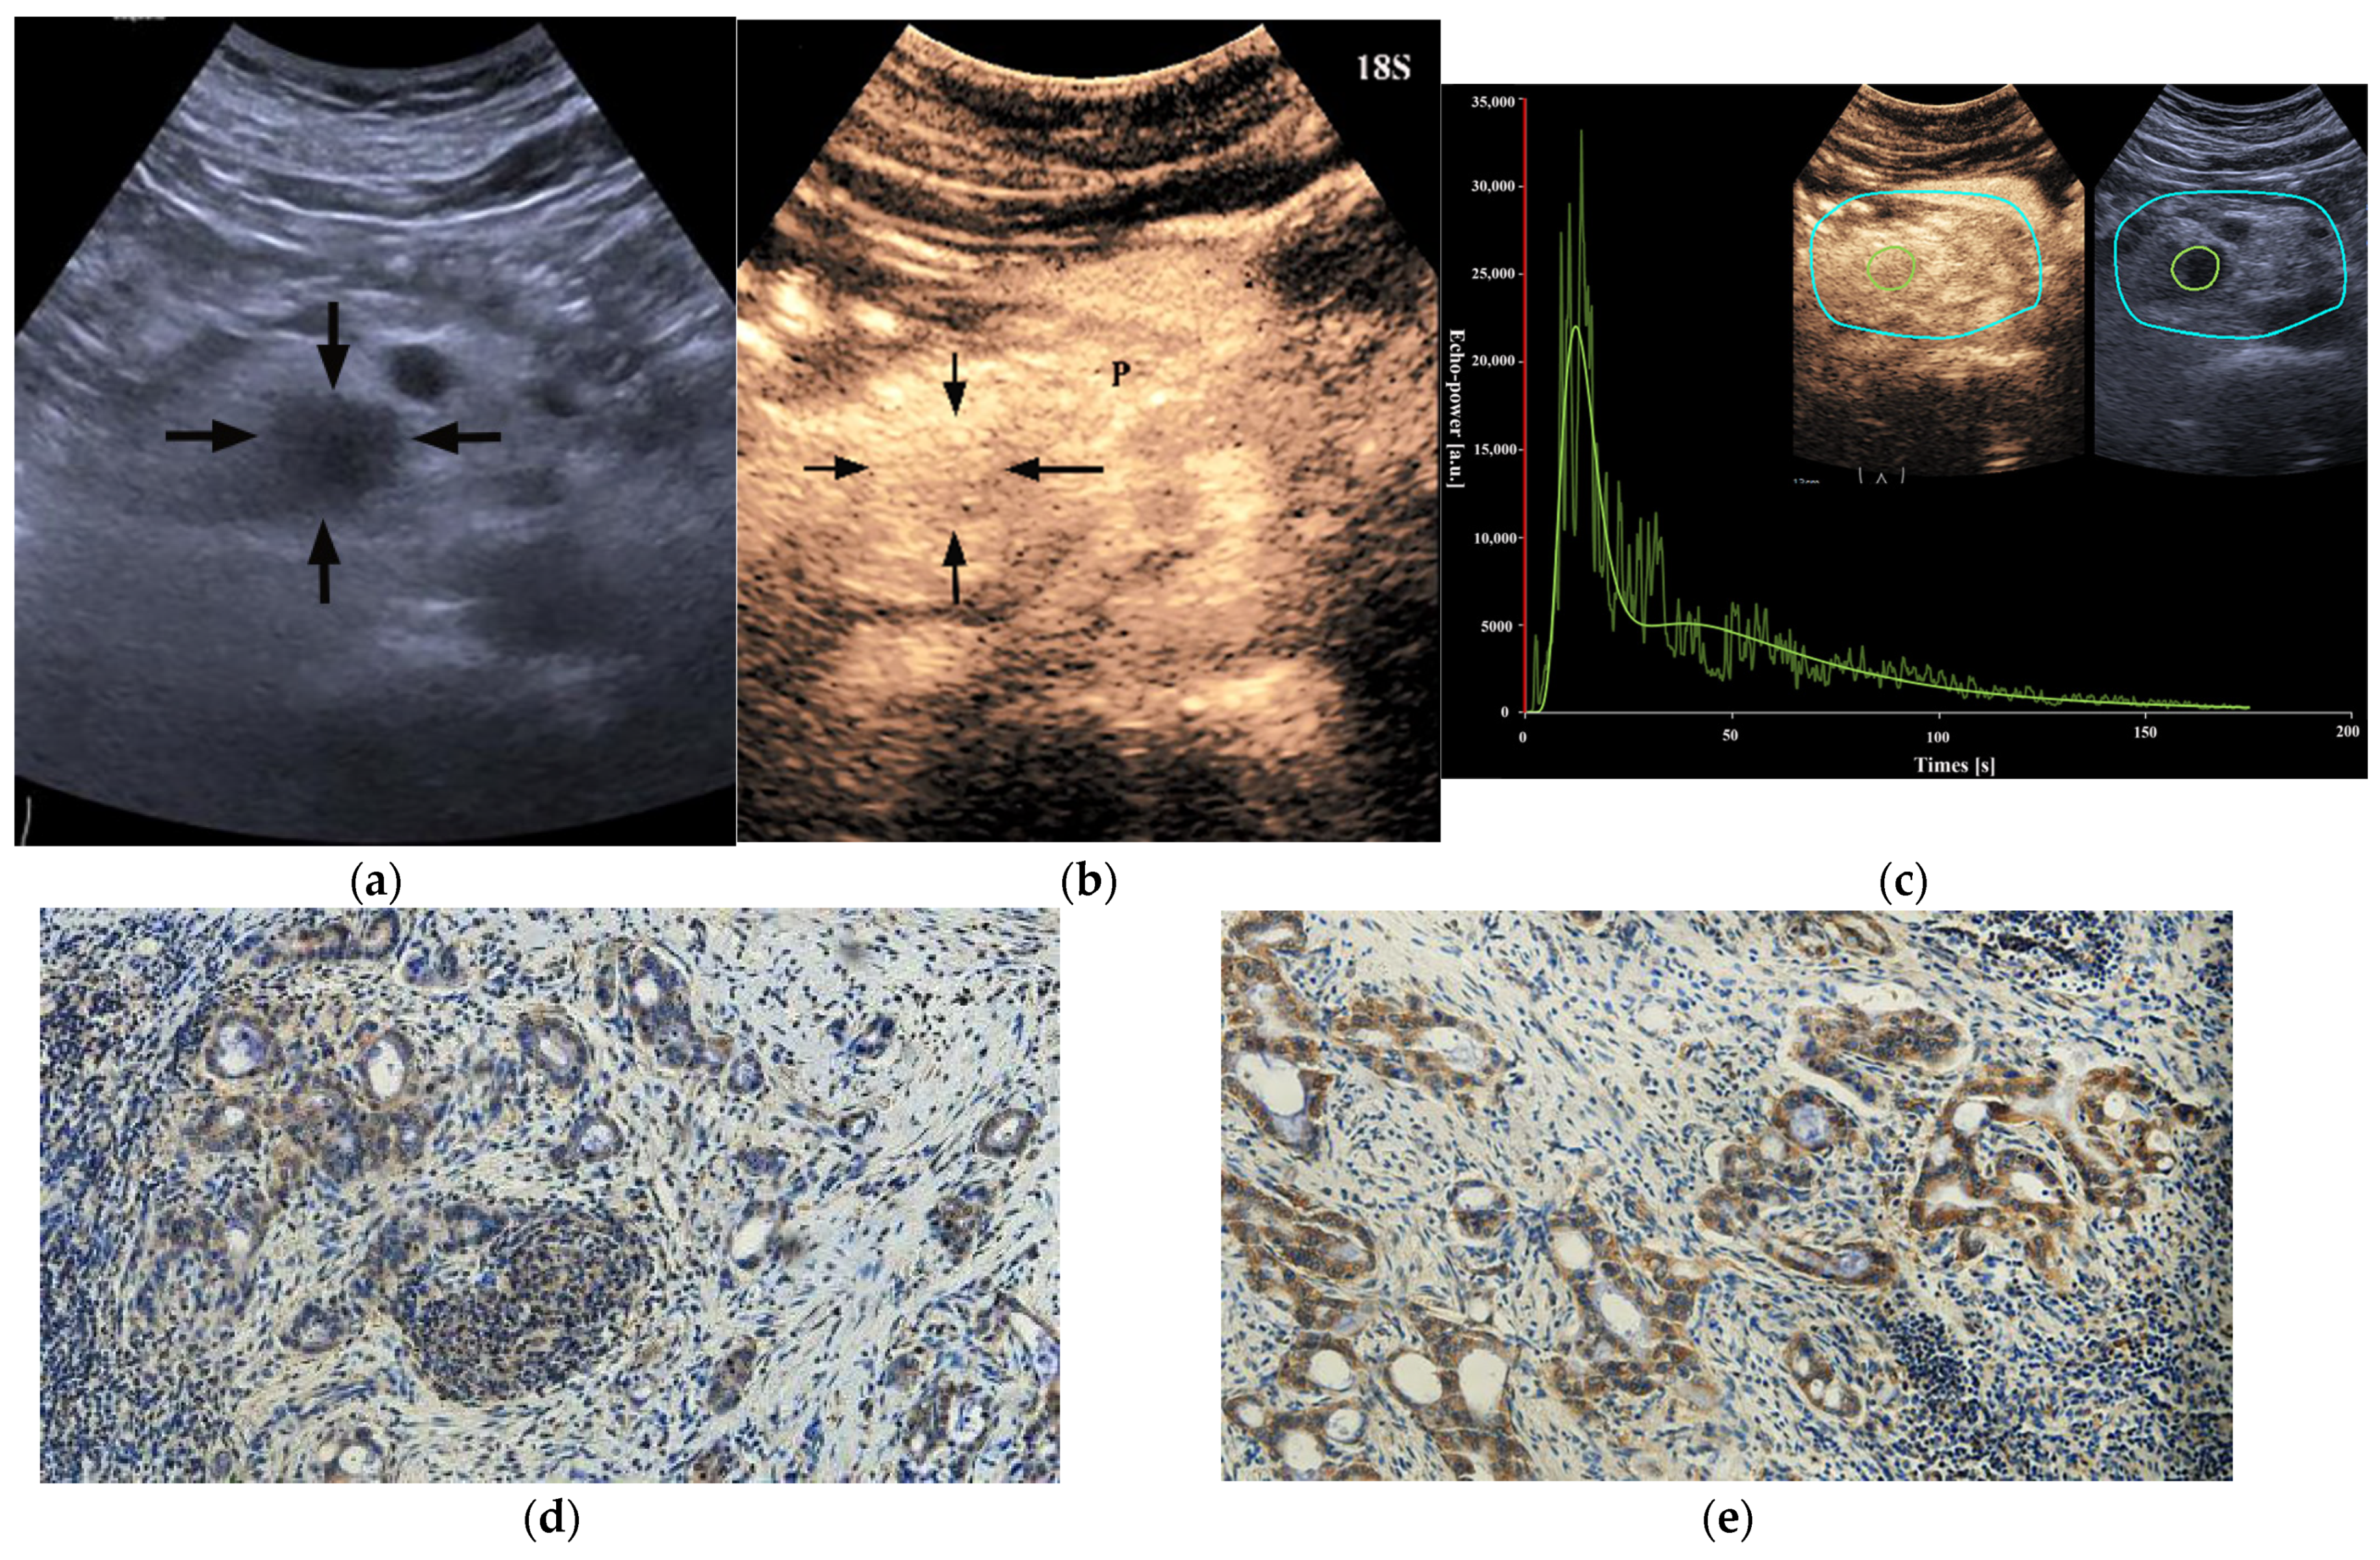

HIF-1α-high PDACs (p = 0.001) and GLUT1-high PDACs (p = 0.003) manifested incomplete enhancement more frequently on CEUS (Figure 2 and Figure 3). In PDACs with ≤50% enhancement, 80% (12/15) showed HIF-1α high expression and GLUT1 high expression. The peak enhancement degree (PED) in HIF-1α-high PDACs (p = 0.027) and GLUT1-high PDACs (p = 0.008) showed iso-enhancement more frequently (Figure 2 and Figure 3) (Table 2).

Figure 2. A 29-year-old male patient with a pancreatic ductal adenocarcinoma. (a) US revealed a hypoechoic lesion (arrows) at the pancreatic head. (b) The lesion (arrows) demonstrated incomplete enhancement (enhancement > 50%) on CEUS and the peak enhancement degree of the solid component was iso-enhancement. P = normal pancreatic parenchyma. (c) Photomicrographs of immunohistochemistry stain sections demonstrate a HIF-1α high expression ductal adenocarcinoma (original magnification, ×200). (d) Photomicrographs of immunohistochemistry stain sections demonstrate a GLUT1 high expression ductal adenocarcinoma (original magnification, ×200).